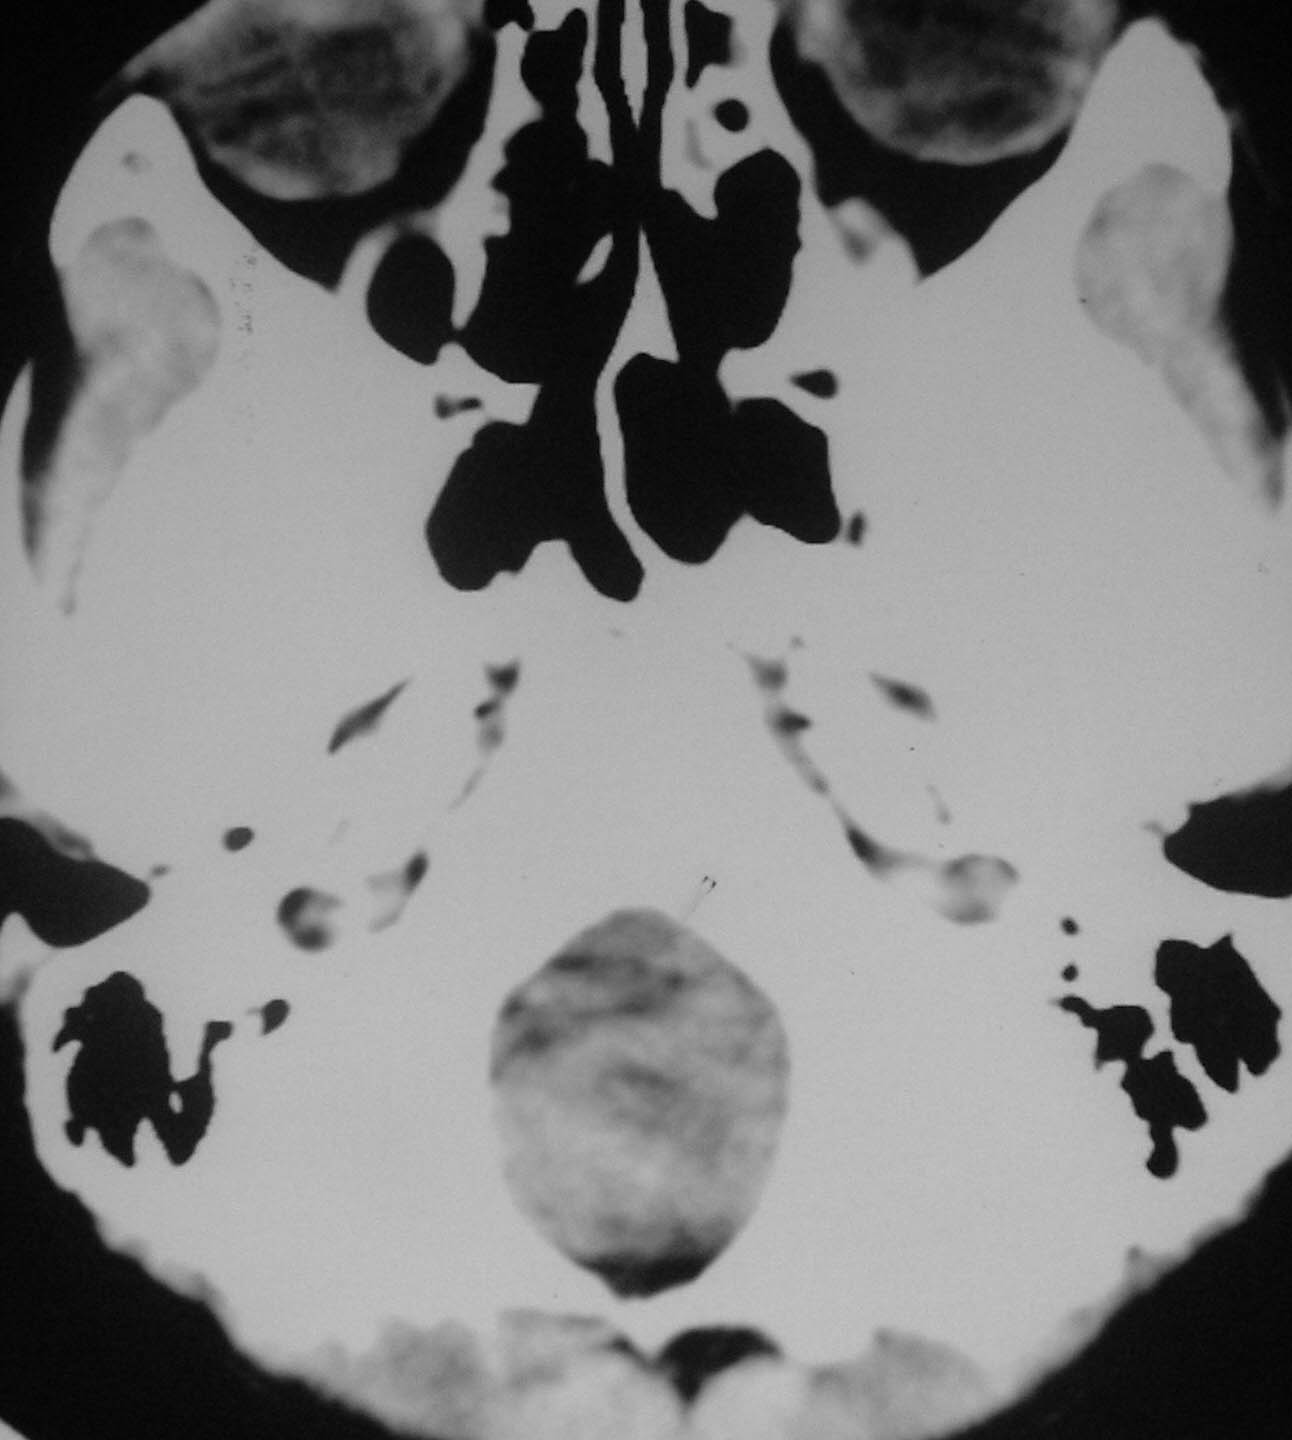

以下是引用余辉在2007-4-28 19:55:00的发言:[br]血管畸形?增强一下

以下是引用jw-830在2007-4-28 20:22:00的发言:[br]考虑血管畸形可能建议增强

以下是引用ysxyy在2007-4-29 21:14:00的发言:[br]像是假像,如果不放心可以偿试一下:[br]你用听眦线为基线扫一下,再用听眶线扫一下,就是说用不同的角度扫同一个地方;[br]看看有无变化,是不是有相同或相似的表现,即可鉴别;